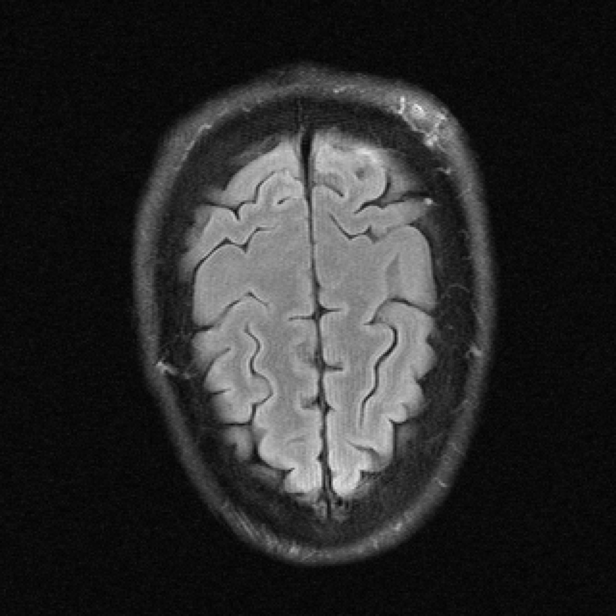

| Ground Truth | E2E-VarNet | UDNO | Nirvana (Ours) |

We also visualize the performance of Nirvana for MRI reconstruction with the undersampling rate set as 8 in Fig. 3. The ground truth, the images reconstructed by E2E-VarNet, UDNO, and Nirvana are shown in the 4 columns, respectively. As shown in Fig. 3, the performance of Nirvana is better than UDNO and E2E-VarNet in terms of the image fidelity and resolution. The reconstructed image of E2E-VarNet is blurry, and some part of the brain is completely obscured by black patches. The reconstructed image of UDNO is roughly close to the ground truth image, but the resolution is low and the details of the image are unclear. However, the reconstructed image of Nirvana is clear and accurate with high resolution, remarkably resembling the ground truth image with the highest SSIM, whose value is 0.8812.